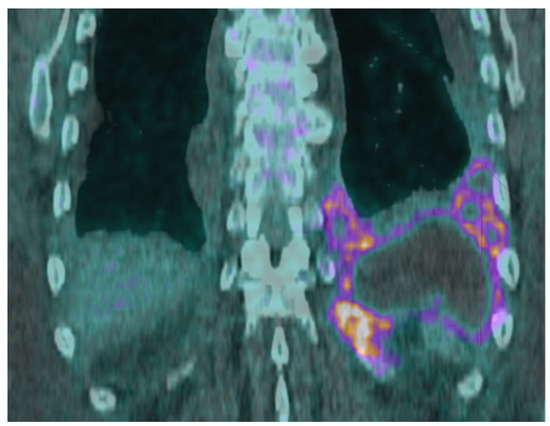

2. Case Presentation